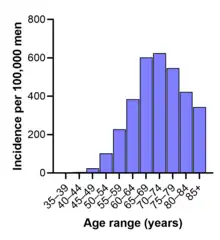

Fréquence

Les taux de ce cancer varient considérablement de par le monde. Il est moins répandu en Asie du Sud et en Extrême-Orient, plus commun en Europe et encore plus aux États-Unis. Selon la Société américaine du cancer, ce cancer est plus rare chez les Asiatiques et plus répandu chez les personnes d'origine subsaharienne (les taux élevés pouvant aussi être influencés par l'accroissement de l'effort de détection).

Le cancer de la prostate survient le plus souvent après cinquante ans. Il est globalement le second cancer le plus fréquent chez l'homme, et, dans certains endroits[5] (dont en France[6],[7]), il prend la première place, devant le cancer des poumons (qui est cependant plus souvent mortel). De nombreux porteurs d'un cancer de la prostate n'éprouvent jamais de symptômes, ne subissent aucune thérapie et meurent pour d'autres raisons. De nombreux facteurs d'origine génétique, toxicologique et liés au régime alimentaire semblent impliqués dans le développement de ce cancer.

Les études autoptiques confirment une haute prévalence de cancers asymptomatiques et non diagnostiqués de la prostate chez les hommes dès 30 ans[8]. Cette prévalence augmente avec l'âge, atteignant environ la moitié des hommes de type caucasien au-delà de 80 ans[8]. On retrouve des foyers de cellules cancéreuses dans 30 à 70 % des cas lors d'études autoptiques réalisées chez des hommes de 70 à 80 ans ; le cancer de la prostate reste néanmoins le plus souvent asymptomatique.[réf. nécessaire]

Son incidence augmente (en partie apparente à cause d'un meilleur dépistage). C'est ainsi en France le cancer dont l'incidence a le plus augmenté de 1980 à 2005 (+6,3 %), avec une augmentation annuelle encore accrue de 2000 à 2005 (+8,5 %). Il explique à lui seul environ 70 % de l'augmentation totale du cancer chez l'homme en France sur ces 25 dernières années. Ceci s'explique pour une grande partie, mais pas totalement, par un meilleur dépistage (Cf. dosage plus systématique du PSA ou « Prostate-specific antigen » en France, depuis la fin des années 1990. Ce dosage nécessite cependant une vérification car l'AFSSAPS n'a trouvé en 2005 que 7 dispositifs de dosage fiables et « acceptables » sur 37 commercialisés)[9].

En 2005 aux États-Unis, on estime que 230 000 nouveaux cas de ce cancer sont apparus et 30 000 décès sont dus à celui-ci[10].

En France, le dernier rapport de 2023 de l' Institut National du Cancer donne les chiffres suivants[1] :

- 59 885 nouveaux cas en 2018 en France métropolitaine

- Taux d'incidence : -1,1 % par an en moyenne entre 2010 et 2018

- Âge médian au diagnostic en 2018 : 69 ans

- Prévalence estimée à 643 156 personnes en 2017

- 8 100 décès en 2018

- Taux de mortalité : -3,7 % par an en moyenne entre 2010 et 2018

- Âge médian au moment du décès : 83 ans

- Survie nette standardisée à 5 ans des hommes diagnostiqués entre 2010 et 2015 : 93 % (stable)